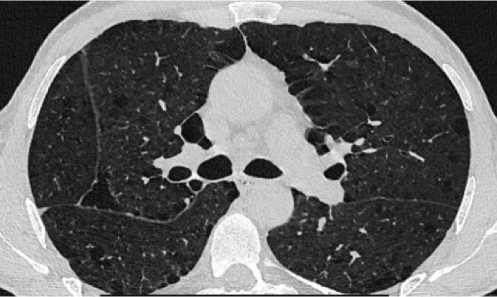

Макроскопически материал (рис. 3) представлен фрагментом лёгкого размерами 9,0×6,8×4,2 см с наличием на разрезах плотного сероватого очага с черноватыми участками размерами 5,5×5,0×3,0 см с фокусами распада. Также отмечались мелкие черновато-серые очажки, и, кроме того, буллы протяжённостью до 1,5–1,7 см.

При патогистологическом исследовании операционного материала в лёгочной ткани обнаружены немногочисленные разнокалиберные очаги эозинофильного некроза (рис. 4а), часть из которых с неравномерно выраженной лейкоцитарной реакцией. Также отмечались макрофагальногигантоклеточные гранулёмы, в том числе в стенках бронхиол. Кроме того, выявлены эмфизематозные изменения лёгочной ткани в виде субплеврально расположенных тонкостенных полостных образований – булл (рис. 4б). Вместе с тем в лёгком и лимфатических узлах (внутрилёгочном и внутригрудных) были обнаружены множественные очажки гипокле-точной фиброзной ткани слоистого строения с отложениями угольного пигмента – кониотические узелки (рис. 4в, рис. 4г).

а

Рисунок 3. Макропрепарат операционного материала: а – из операционной после удаления; б – нарезка материала для парафиновых блоков: фрагменты лёгкого размерами с наличием на разрезах плотного сероватого очага с черноватыми участками, также мелкие черновато-серые очажки, и, кроме того, буллы

Figure 3. Macro-preparation of the surgical material: a – from the operating room after removal; б – cutting of the material for paraffin blocks: fragments of light size with the presence of a dense grayish focus with blackish areas on the incisions, as well as small blackish-gray foci, and, in addition, bullae

б